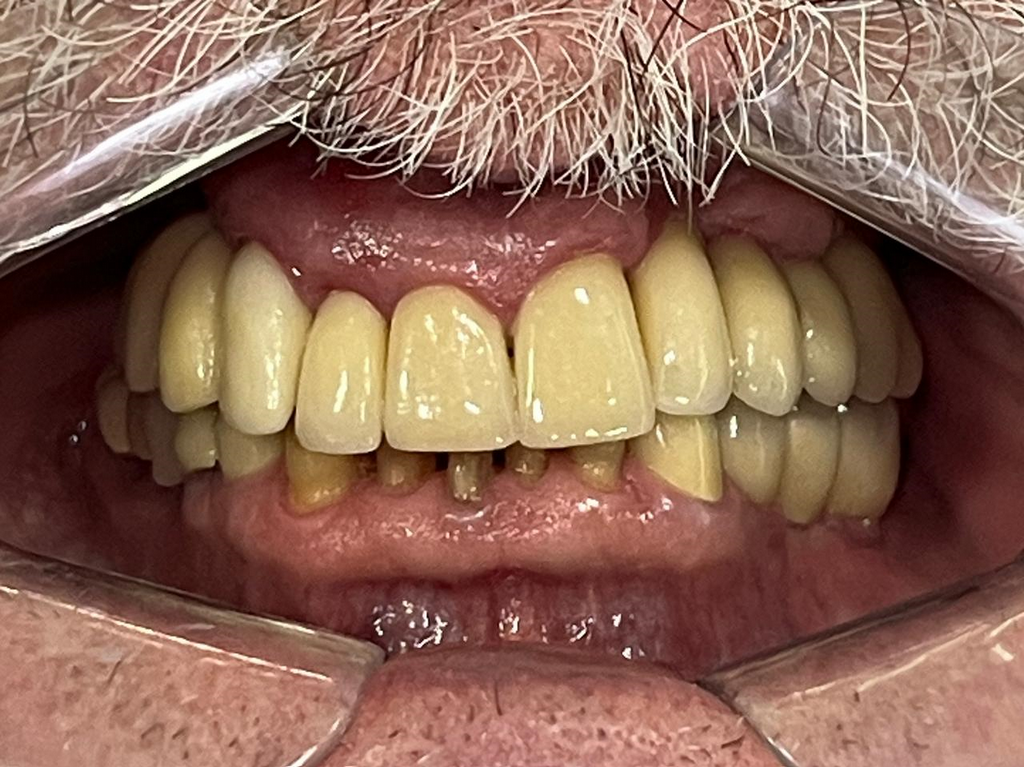

PRÓTESE TOTAL FIXA EM IMPLANTES

M.A.V.J.